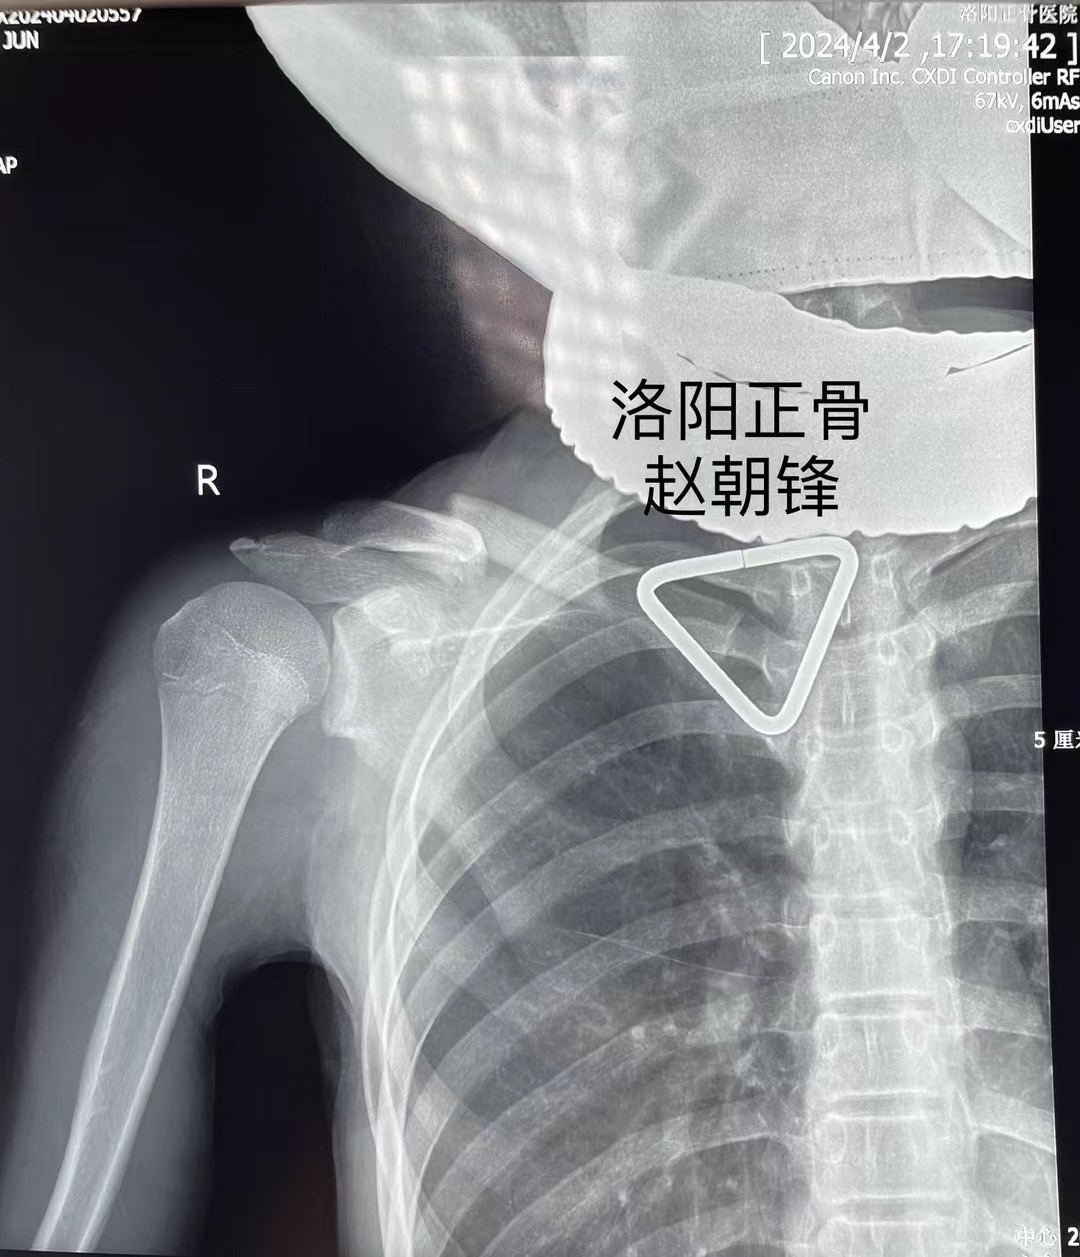

谢先生的孩子,小谢同学今年15岁,在跑着玩耍时摔倒,造成右肩部肿痛、活动受限,拍片显示右锁骨骨折,错位明显,辗转多家医院就医,均表示要开刀,放入钢板固定,但是小谢同学将来要报考军校,多年梦想,不想因为一朝骨折就放弃,于是慕名来到我院,找到手法正骨二科(微创正骨二科)主诊组长赵朝锋,经过制定详细的手术方案,主诊组长赵朝锋建议采用“手法复位、闭合穿针”治疗,这种方法具有创伤小、愈合快、功能恢复好、无皮肤切口瘢痕等诸多优点,在术后换药时,谢先生仔细观察了孩子的伤口:“没有切开皮肤,只在皮肤上留下了几个小眼,效果真好!”